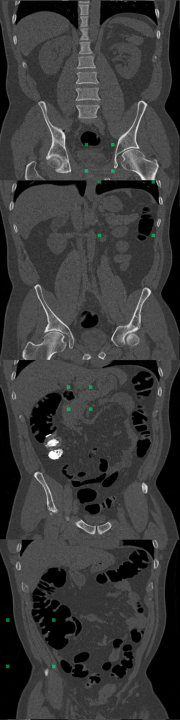

MOOD Datasets (Zimmerer et al. (2020)): the MOOD challenge provides two datasets, 800 brain MRI volumes (256x256x256) and 550 abdominal CT volumes (512x512x512). Each subject is positioned in approximately the same way, but non-rigid registration is not used. As such, the same voxel/location in two different volumes may contain different tissue. All samples are assumed to be healthy with no abnormalities. Given that no test data is provided, we reserve 10% of the data as healthy test cases and we use 30% of the data to create anomalous test cases. The remaining 60% of the data is used for training. To create the anomalous test set, we synthesize five types of outliers. In each case a sphere of random size and location is selected within each volume; the pixels within that sphere are altered in one of five ways listed below. An example of a sink/source synthetic outlier is given in Figure 2. Performance is evaluated using average precision (AP), which is the metric originally used in the MOOD challenge (Zimmerer et al. (2020)). We also include evaluation with area under the receiver operating characteristic curve (AUROC) and an estimated DICE score (). To compute an approximate DICE score, pixel-level anomaly scores are converted to binary segmentation masks. Following Baur et al., a greedy search is used to find an ideal threshold for this conversion (Baur et al. (2021)).

DeepLesion Dataset (Yan et al. (2018a)): this dataset contains CT scans from 4,427 unique patients exhibiting a broad range of lesions. There are at least eight different types of lesions including lung, abdomen, mediastinum, liver, pelvis, soft tissue, kidney, and bone. Each lesion is annotated with a bounding box. This dataset also includes volumetric data with slices above and below the annotated slice, typically about 30mm on both sides. In many cases, there are multiple annotated slices contained within one volume. To extract normal data from these volumes, we remove all annotated slices along with a margin about 10mm on either side. We train on 270,561 normal slices and test on 116,026 normal slices and 4831 annotated slices with lesions. A supervised benchmark is also trained using 22,496 slices with lesions and corresponding bounding box labels. Image-level testing uses normal slices and slices containing lesions. However, for pixel-level evaluation we only use slices with lesions. In this case, pixels inside bounding boxes are considered anomalous and all pixels outside of the bounding boxes are considered normal. All images are resized to 256x256. Performance is evaluated using AUROC and . Receiver operating characteristic (ROC) curves are also plotted.

In addition to the synthetic test set, which only includes local abnormalities, we provide examples of global abnormalities in Figure 5. A normal sample produces minimal activation in its canonical orientation (Figure 5, left most image in (a)). However, rotating the sample produces scattered activations throughout the entire volume (Figure 5, (a)). Blurring or substituting different anatomy produces even stronger activations (Figure 5, (b)).